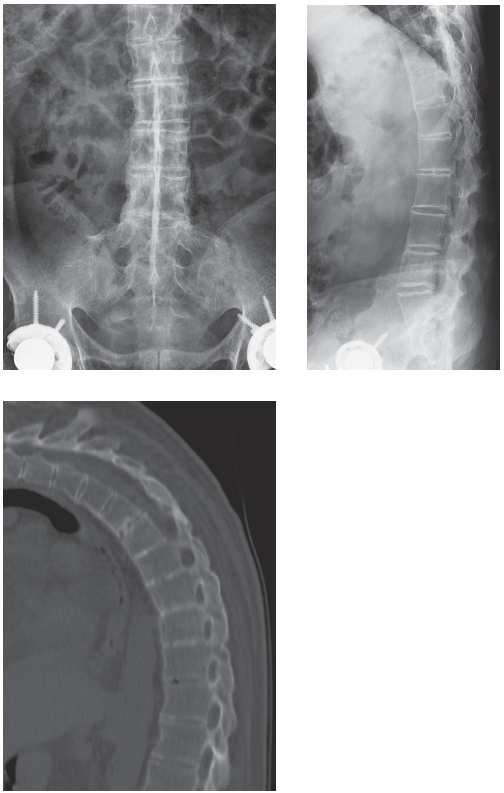

이 케이스는 'Aunt Minnie'이다. 강직성 척추염의 틀림없는 특징은 단순 방사선 영상과 시상면 CT에서 명백히 드러난다. 강직성 척추염은 가장 흔한 혈청검사 음성형의 척추관절병증(seronegative spondyloarthropathy)이고 남성에서 압도적으로 많다. 질환의 발병은 15~35세 사이에서 발생하고 90% 이상이 HLA-B27 양성이다. 임상적으로 이러한 환자들은 요통과 강직이 존재한다. 질환이 진행됨에 따라 현저한 흉추후만과 제한된 요추전만이 두드러지게 나타난다.

천장관절은 전형적으로 첫번째로 연관되는 부위이며 천장관절염이 이 질환의 특징에 해당한다. 관절의 장골 부위에서 초기 주위 관절의 골다공증과 표층 피질의 미란이 관절강이 넓어짐의 결과가 나타나는 좀더 극적인 미란성 변화 뒤에 나타난다. 상아질화(Eburnation)는 경화증의 치밀한 병소 제한적인 띠로써 발전한다. 증식성의 변화가 더 현저해짐에 따라 불규칙한 골성 가교가 결국 전체 관절 강직증을 초래한다. 이러한 모든 발견은 인대와 관절의 윤활 부분 둘다에서 발생한다.

'대나무 척추(Bamboo spine)'라는 용어는 인대증식체(섬유륜의 골화)의 과도한 증식의 존재로 특징지어질 수 있다. 트롤리-트랙(Trolley-track) 징후는 전방 방사선 영상에서 보이며, 극상인대와 극간인대와 골단관절낭의 골화와 일치하는 세 수직 방향의 치밀한 선을 의미한다. 트롤리-트랙(Trolley-track) 징후는 극상인대와 극간인대의 골화를 나타내는 전방 방사선 영상에서 단일 방사선 라인으로 나타나는 단검 징후(dagger sign)에 비해 앞설 수 있다.